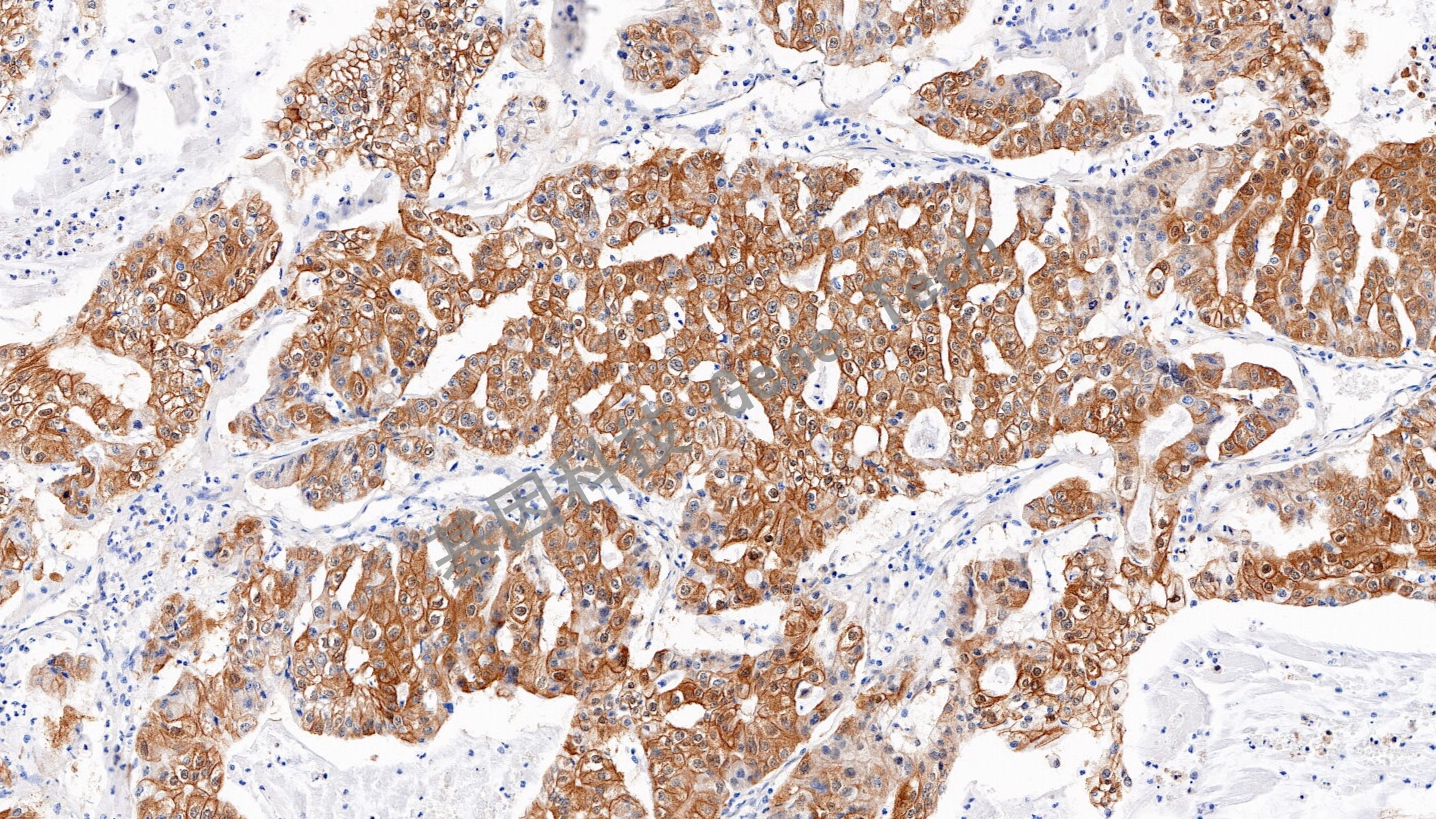

| 肝癌石蜡切片,用 AKR1B10(GT2563)染色,细胞浆阳性,DAB 显色。 | ||

| 预处理:高pH热修复 | 阳性部位:细胞浆 | 阳性对照:肝癌 |

| 简介:醛酮还原酶家族1成员B10((aldo-keto reductase 1B10,AKR1B10),主要功能是还原醛酮类羰基化合物、促进脂质合成和调节视黄酸代谢。AKR1B10首先发现于肝癌中,在正常人体组织中主要表达于胃肠道组织,在其他组织中低表达或不表达。研究表明AKR1B10在肿瘤的发生发展过程中发挥重要的作用,在许多上皮性肿瘤中出现了过表达的现象,如乳腺癌、宫颈癌、肺癌等。因此AKR1B10可能成为肿瘤诊断非常有价值的分子标记物以及靶向治疗肿瘤的新靶点。 | ||